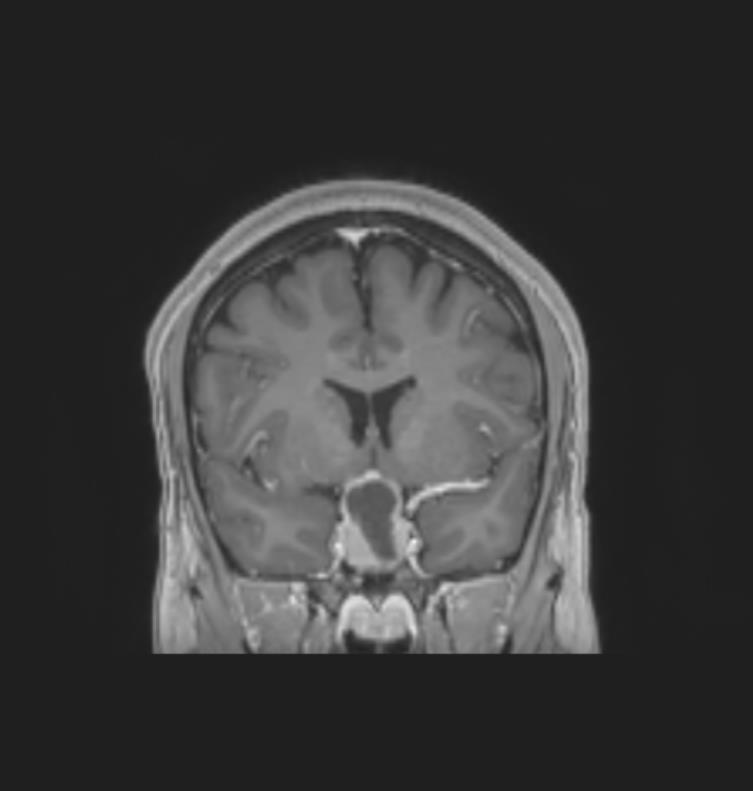

Le patient bénéficie également d’une imagerie par résonance magnétique (IRM) cérébrale devant un doute sur le scanner. Voici deux coupes (figures 2 et 3) :

Figure 2 (source : G. Kielwasser)

Sur la coupe coronale d’IRM en séquence T1 avec injection de gadolinium ci-dessous (figure 2 bis), on constate :

– sur l’image de gauche, que les sinus caverneux sont visibles de part et d’autre de la fosse pituitaire avec les vaisseaux rehaussés par le gadolinium. La flèche jaune pointe la masse hétérogène (centre hyposignal, périphérie hypersignal), en lien avec l’apoplexie pituitaire qui correspond à une hémorragie au sein du macro-adénome hypophysaire ;

– sur l’image de droite, que la ligne rouge correspond à une limite approximative de la loge pituitaire que l’hypophyse ne devrait pas dépasser. La flèche verte pointe le chiasma optique comprimé par la masse.